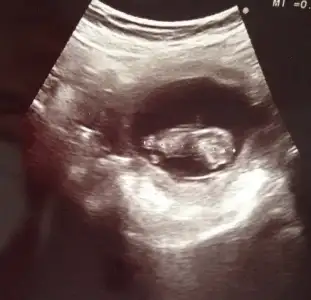

Cinsiyet tahmini yapan arkadaşlar benim bebişime de bi tahminde bulunun :)